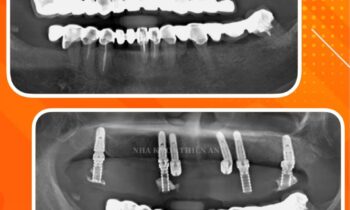

CẮM IMPLANT- PHƯƠNG PHÁP THAY THẾ RĂNG MẤT HIỆN ĐẠI NHẤT TẠI NHA KHOA THIỆN AN

Tiếp tục trồng răng implant cho quý khách hàng thân yêu của nha khoa Thiện An BMT – Đăk Lăk, chúc mọi người một ngày làm việc tràn đầy năng lượng ạ Cấy ghép Implant là phương pháp duy nhất giúp ngăn chặn biến chứng tiêu xương cùng nhiều vấn đề răng miệng khác sau…